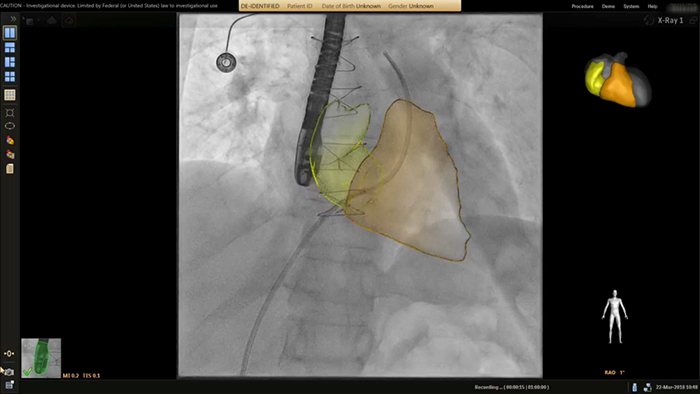

ASD closure with EchoNavigator live fusion